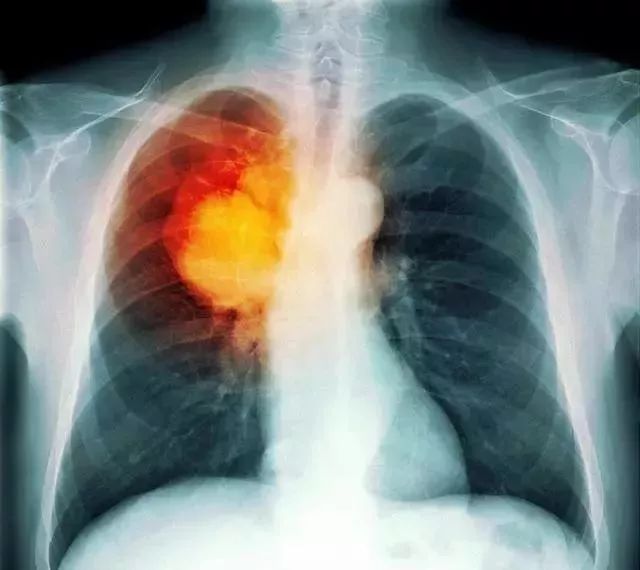

经检查,医生确诊女孩已经到了肺癌晚期,已没有任何希望了。

亚硝胺这类毒物会造成人体细胞DNA损伤,这种DNA损伤会导致细胞不受控制的生长,最后形成肿瘤,也就是癌症!

根据国家癌症中心发布的《 2017 中国肿瘤登记年报》显示,在中国,每分钟就有7个人被确诊得癌。

无论从发病率和死亡率来看,肺癌在中国均高居第一。

中国占了世界1/5的人口,全世界1/3肺癌患者在中国,就因为1/3的烟民在中国!